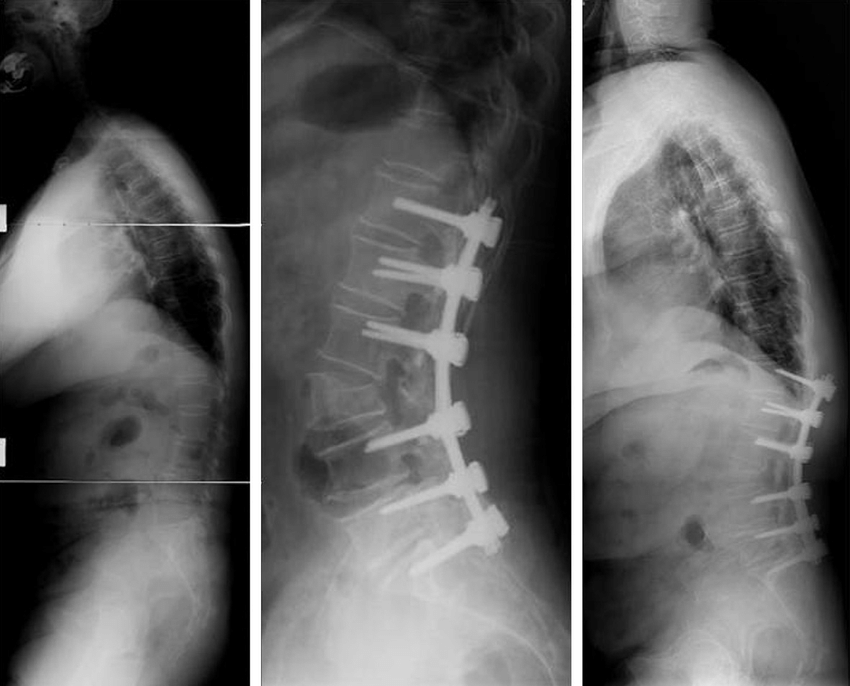

수술적으로는 C7 plumb line이 전방으로 전위된 positive balance 를 교정해주어야 합니다.

PSO (pedicle subtraction osteotomy), posterior correction, posterior correction c PLIF, ant & post correction 등을 시행해 볼 수 있습니다. 주의할 것은 골반의 보상이 불가능한 경우에는 교정술을 시행하면 안됩니다.